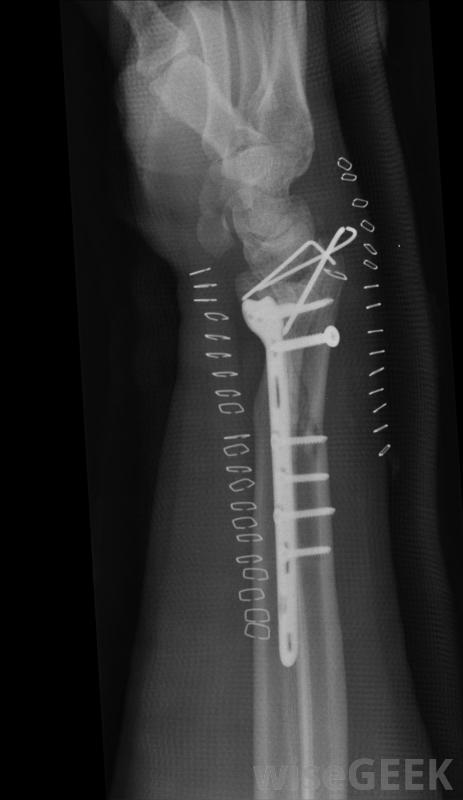

三踝骨折可导致瘀伤。三踝骨折的外科治疗通常包括使用当骨折愈合时,用来固定骨折的金属板、螺丝钉或金属丝。在骨折牢固融合在一起之前,脚踝不可能承受重量,这可能需要四个月的时间,在这段时间里可以拍X光片来检查骨骼是否没有移位,一旦有可能移动脚踝,建议进行一系列的锻炼来加强关节周围的肌肉

通常会对骨折进行X光检查三踝骨折的外科治疗通常包括使用金属板和螺钉或金属丝将骨折固定在一起鞋子有助于防止许多三踝骨折。